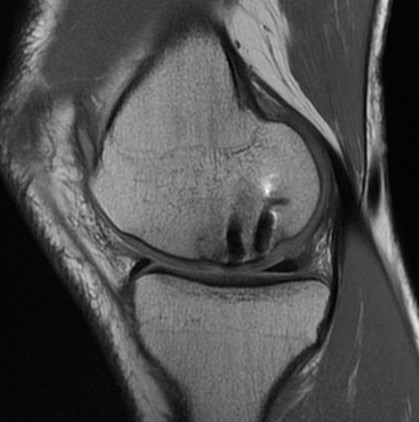

MFC OCD on presentation T2 image 6 months later

T1 sagittal on presentation T1 sagittal six months later

Progression of reossification over 6 months following drilling